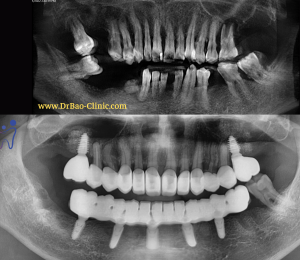

Tình trạng răng ban đầu

👨⚕️ Khám lâm sàng chúng tôi nhận thấy:

👉Chị có triệu chứng mỏi 2 bên cơ cắn, do nâng khớp quá nhiều miệng luôn trong tư thế há.

👉Đường cong cắn khớp không đúng, cong ngược so với bình thường.

👉Nướu răng trước hàm trên viêm đỏ, chảy máu – Hậu quả của việc cắt nướu nhưng không điều chỉnh xương ổ răng.

👉Không có vị trí cắn khớp tối đa cố định giữa 2 hàm.

🚎🚎Sau khi được giải thích kĩ trên mẫu hàm, phim, hình ảnh và nhiều ngày suy nghĩ (chắc thấy bác sĩ gì mà nhỏ quá😅) chị đồng ý với kế hoạch điều trị gồm:

👉Cắt bỏ sứ cũ.

👉Tái lập khớp cắn và đường cong cắn khớp và mang răng tạm nhựa PMMA.

👉Phẫu thuật điều chỉnh xương ổ răng trước trên điều trị viêm nướu.

👉Phục hồi lại bằng mão Zirconia rời cho 2 hàm.